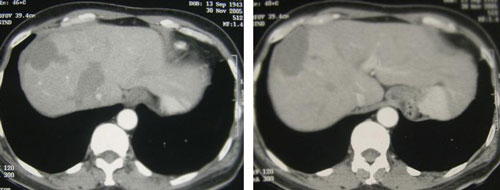

Putrinya memberitahu kami bahwa May menderita nyeri yang tidak tertahankan. Ketika ia tidak tahan dengan nyerinya, ia melepas pakaiannya dan lari mengelilingi rumah. Pada satu waktu May mencoba untuk melompat dari jendela untuk bunuh diri. Lengan dan daerah sekitar payudara dan lengannya bengkak dan mengeras. Ia merasa sangat panas dari dalam tubuhnya. Ia memutuskan untuk menyerah dari terapi medis lebih lanjut dan mencari kamu untuk pertolongan pada akhir Juli 2006. Gambar berikut ini dapat menjelaskan lebih lanjut tentangnya waktu sekarat.